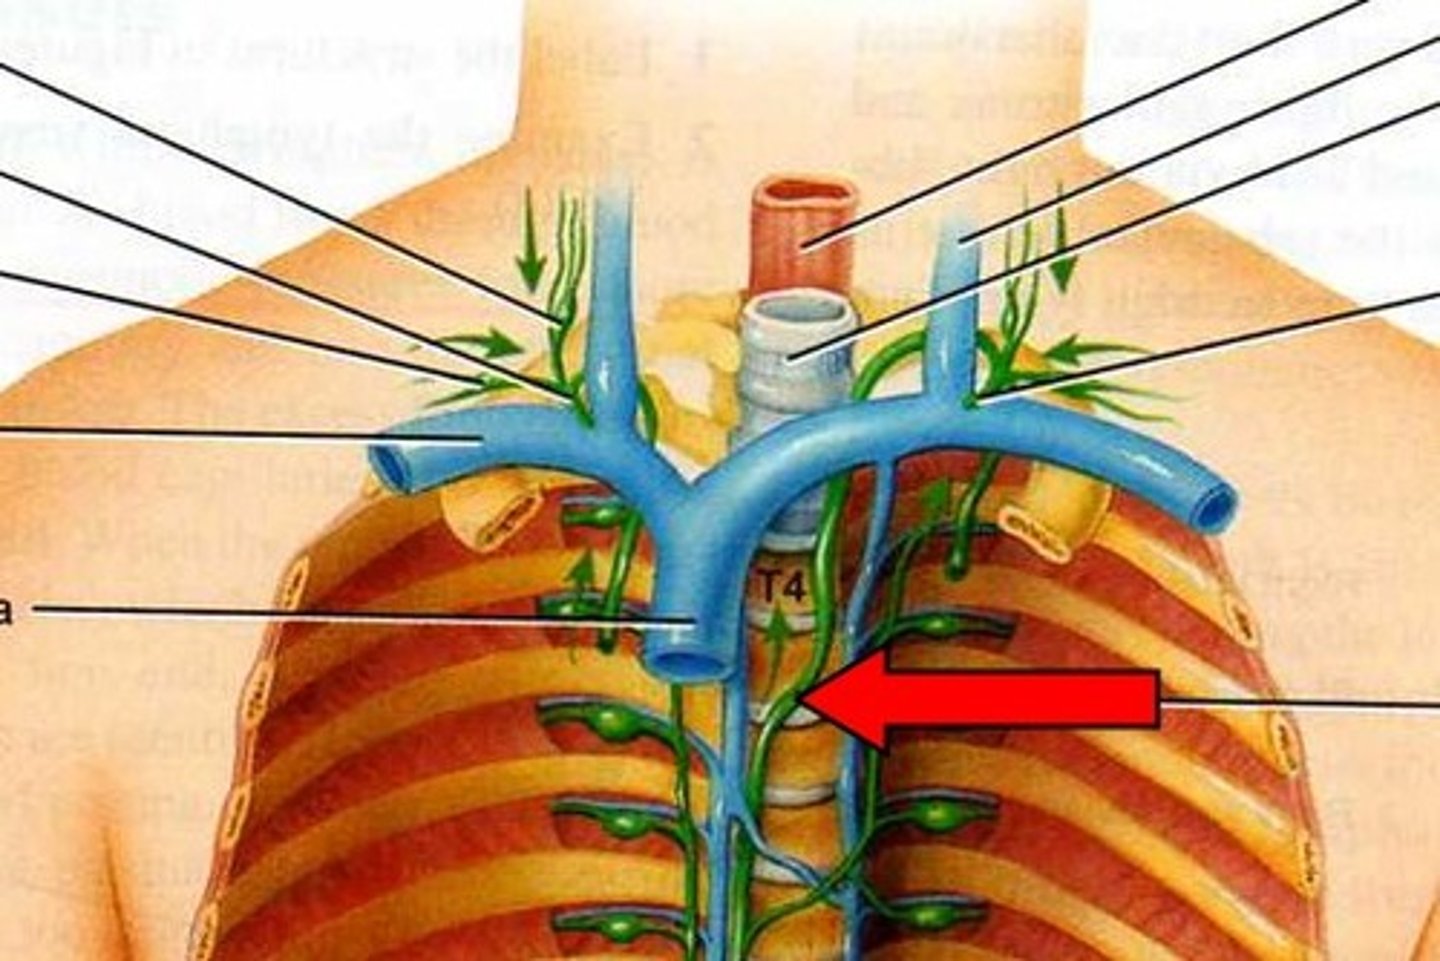

Cisterna chyli

Thoracic duct (left lymphatic duct)

Left or right lumbar trunk